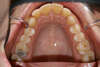

Vues avant le traitement